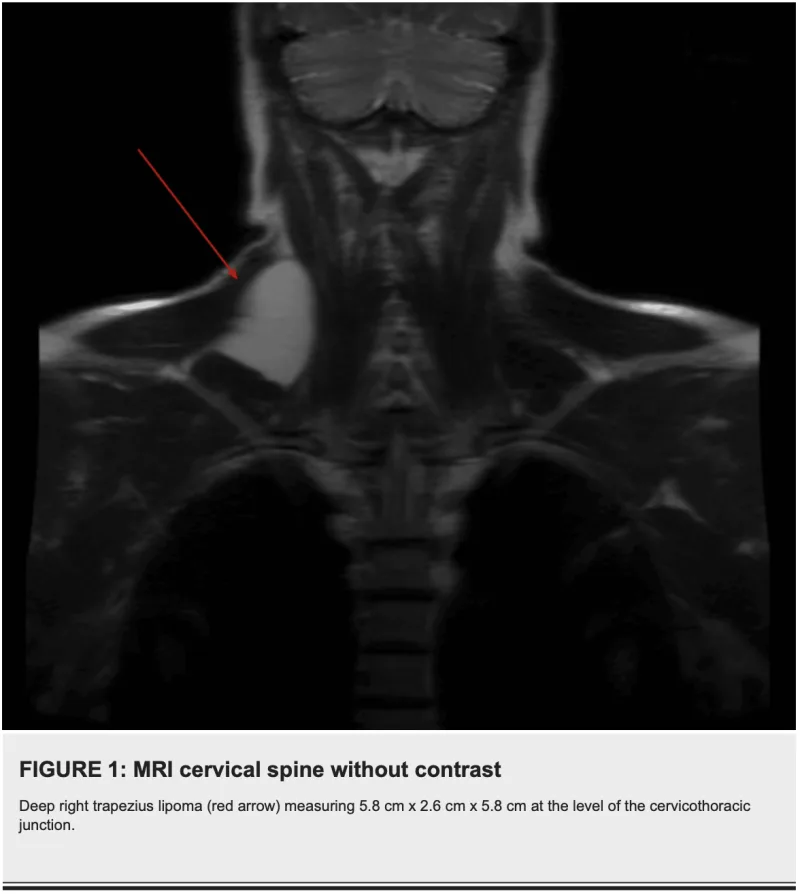

13時半から, 頚部後側方に生じた筋肉内脂肪腫の摘出術.

大学病院の後輩医師から当科での手術を勧められて紹介された前期高齢患者さんでした.

腫瘍は僧帽筋の深部に局在.

筋切開が必要なため, 全身麻酔を選択.

4cmの最小切開で摘出し, 予定通り40分で終了しました.